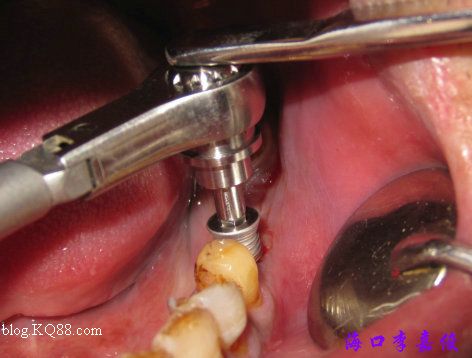

36種植窩成形后要植入4.8X13mm植體

37種植窩成形后植入4.8X10mm植體